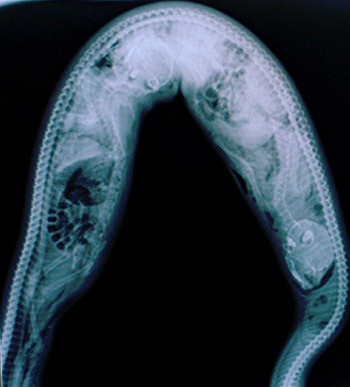

Người dân đã quyết định bắt và mổ bụng con trăn, chỉ để phát hiện ra thi thể của Salubiro ở trong đó. Con trăn đã nuốt chửng chàng thanh niên. Và một người trong làng xác nhận, hình như ông ấy đã nghe thấy tiếng kêu cứu phát ra từ lùm cọ vào đêm hôm trước.

Một con trăn gấm Đông Nam Á có lẽ chỉ mất vài phút để giết chết một người trưởng thành. Nhưng để nuốt được hoàn toàn nạn nhân, nó sẽ phải mất cả tiếng đồng hồ. Quá trình tiêu hóa thậm chí diễn ra lâu hơn thế, có thể lên tới vài tuần.

Đó là lý do tại sao các nạn nhân thường được tìm thấy gần như nguyên vẹn bên trong bụng trăn, sau vài ngày mất tích. Có điều, tất cả họ đã hoàn toàn tắt thở và không còn cơ hội sống.